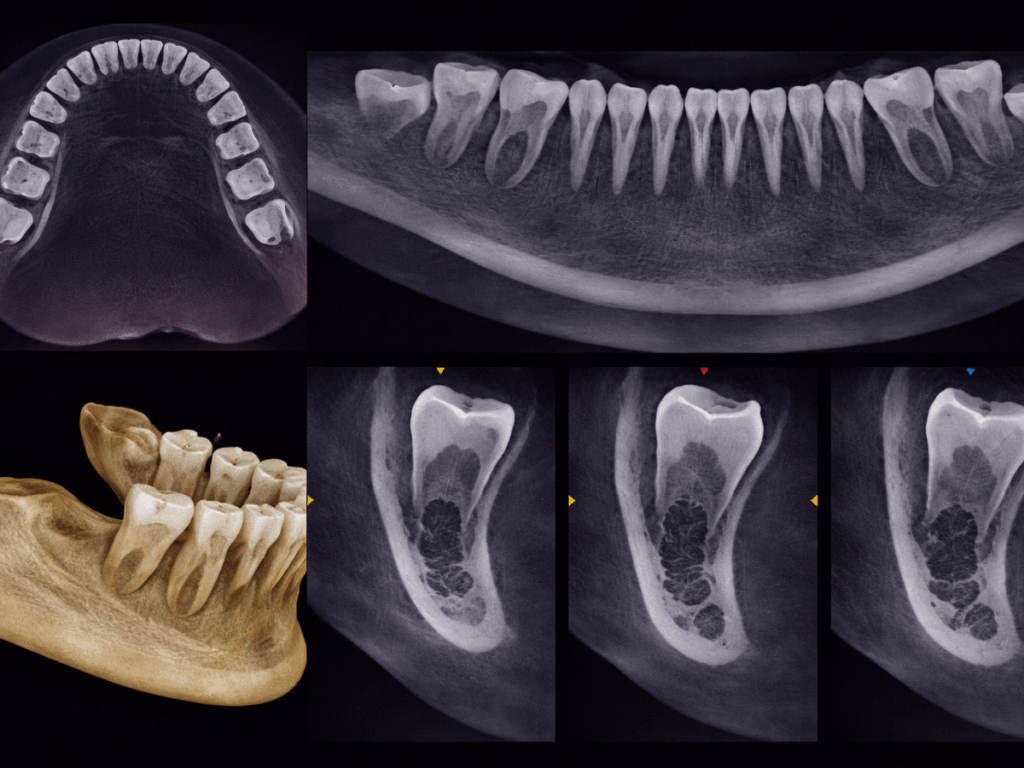

CBCT scans provide detailed, 3D views of your teeth and jaw, making them useful for evaluating many dental conditions. But when it comes to oral cancer, the answer is not always straightforward. Knowing what this technology can and cannot show helps you make more informed decisions about your care.

A CBCT scan creates detailed 3D images of your teeth and jaw, so it can sometimes pick up changes in the bone that may need a closer look. That said, most oral cancers start in soft tissue, which this type of scan does not capture in detail.

A CBCT scan is designed to show detailed images of hard tissues, which helps your provider understand what’s happening beneath the surface.

- 3D views of the jawbone and surrounding structures: CBCT imaging provides detailed, three-dimensional views of the teeth, jawbone, and nearby anatomical structures. This level of detail helps dentists evaluate areas that are not as easy to assess with standard 2D X-rays.

- Changes in bone density or structure: The scan can reveal variations in bone density, irregular patterns, or areas of breakdown. These changes do not confirm cancer, but they can signal that something is affecting the bone and needs further evaluation.

- Tumor-related bone invasion: CBCT is particularly useful for identifying whether a tumor has spread into the jawbone. Research shows it has strong accuracy in detecting bone invasion associated with oral cancer, which plays an important role in staging the condition and planning appropriate treatment.

These insights are useful for identifying changes in the bone and guiding next steps, especially when a closer evaluation is needed. Advanced imaging, including 3D dental scans for a more detailed view, helps provide that added level of clarity.